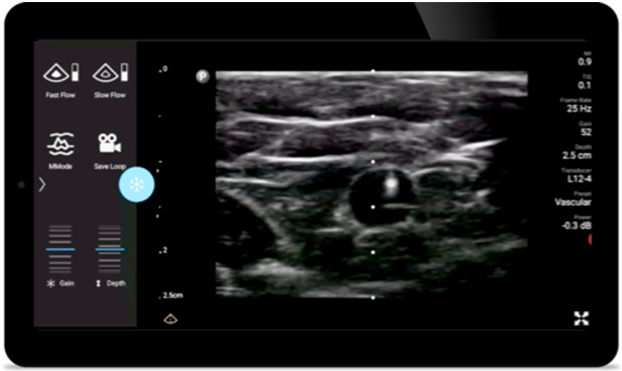

Reduce complications in needle guided procedures

Lumify handheld ultrasound for anesthesiology helps you clearly visualize border definition with your needle placement, surrounding nerves, vessels and fascial planes.

Lumify helps you clearly visualize needle placement, surrounding nerves, vessels and fascial planes.